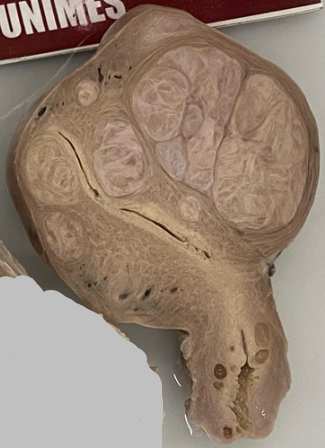

-Órgão: Útero.

-Descrição: Útero aumentado de tamanho, com presença de tumor benigno, bem delimitado com

características semelhante ao do tecido normal.

-Diagnóstico: Leiomioma intramural e subseroso.